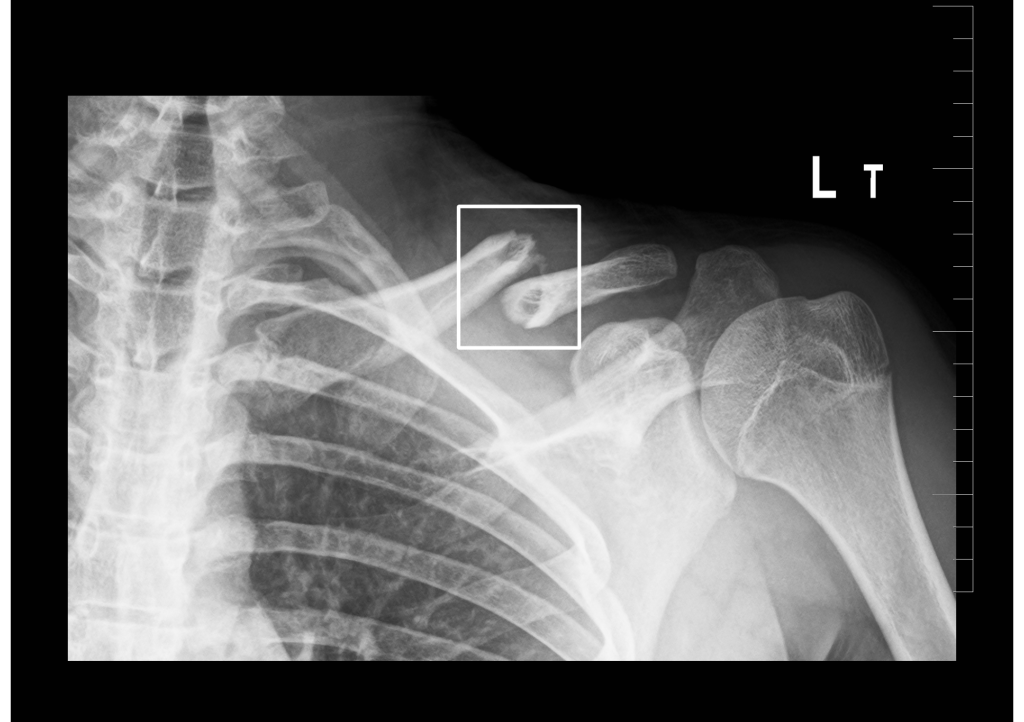

AI systém, ktorý je v nemocnici v prevádzke už niekoľko mesiacov, automaticky analyzuje röntgenové snímky a identifikuje prítomnosť zlomenín. V priebehu pár sekúnd dostane lekár spätný report. „Na obrazovke vidíme vyznačené miesto, kde je nejaká zlomenina alebo prasklina. Softvér dokonca automaticky hodnotí niekoľko projekcií. Nájde miesta, kde vyhodnotí zlomeninu, ale nájde aj miesta, kde je podozrenie, že ide o léziu,“ vysvetľuje prednosta.

Podľa námestníka Úseku medicínskych stratégií MUDr. Štefana Štolfu, PhD., ktorý je ortopédom na Klinike ortopédie a traumatológie pohybového ústrojenstva, je dôležité, aby lekár závery AI skontroloval. „Tu vidím zlomeninu jednoznačne a aj softvér ju presne identifikoval,“ vysvetľuje pri kontrole snímky pacienta. „Sú však prípady, kde je to nejednoznačné, AI indikuje, že na danom mieste môže byť zlomenina, a vtedy sa na to detailne pozrie rádiológ. Môže však ísť o starší úraz,  prípadne zavedený katéter. Umelá inteligencia si to všimne a upozorní lekára, pomáha to pri diagnostike najmä mladším kolegom, ktorí ešte nemajú toľko skúseností“.